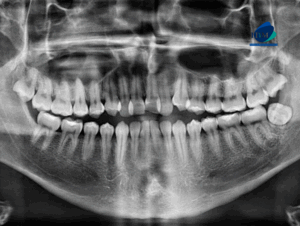

Paciente femenina acude a IDM- Sede Miraflores para evaluar la extracción de terceras molares. Radiografia Panorámica A la evaluación de la radiografía panorámica se observa